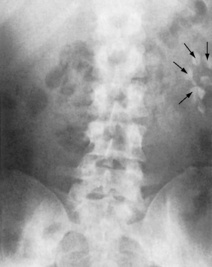

Plain radiography of the kidney, ureters and bladder (KUB) is a simple, non-invasive test that can be used before specialized imaging. It is used to detect calcification in the kidney, such as renal and urinary tract stones – uric acid stones cannot be detected, but in general 90% of stones are radio-opaque (Figs 8.15 and 8.16). It also shows the size and position of the kidneys (this is unreliable), and any secondary bony deposits (such as can be associated with prostatic cancer).

image

Fig. 8.15 Plain abdominal radiograph showing several calculi in the left kidney (arrows).

(Courtesy of Mr RS Cole.)